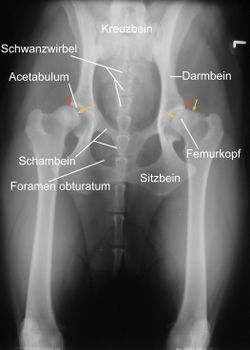

RöntgenEine zuverlässige Möglichkeit zum Erkennen des Schweregrades der Erkrankung bildet die Röntgenuntersuchung. Da bei dieser die Gelenke überstreckt werden müssen, was beim Vorliegen einer HD starke Schmerzen verursacht, wird sie unter einer Kurznarkose durchgeführt. Voraussetzung für eine aussagekräftige Diagnose ist die exakte Positionierung des untersuchten Tieres in Rückenlage mit gestreckten, parallel gelagerten Oberschenkeln und orthograd zum Strahlengang eingedrehten Kniescheiben. Zusätzliche Aufnahmen können in "Froschhaltung" der Oberschenkel oder im seitlichen (latero-lateralen) Strahlengang erfolgen.Röntgenaufnahme einer HD beim Hund. Der Femurkopf ist bereits subluxiert, das Acetabulum (Hüftgelenkspfanne) umgreift ihn nicht mehr (rote Pfeile). Die Femurköpfe zeigen bereits Abweichungen von der Halbkugelform (gelbe Pfeile); rechts im Bild sind deutliche arthrotische Veränderungen des Femurkopfes erkennbar. Anwendung des Norberg-Winkels zur Abschätzung des Schweregrades einer Hüftgelenksdysplasie(englische Bulldogge). Die roten Schenkel geben den minimalen Grenzwert für HD-Freiheit, die gelben Schenkel den tatsächlichen Winkel an. |